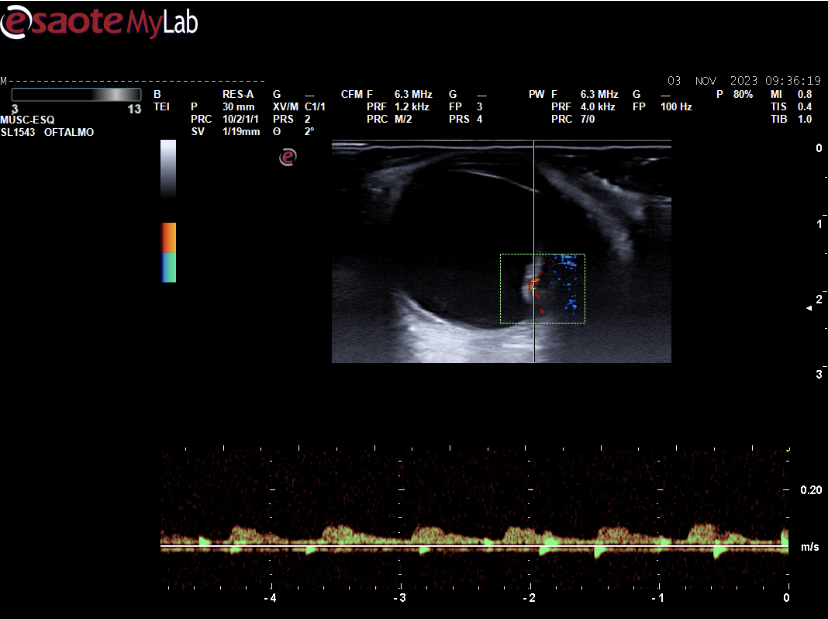

Ecografía ocular: lesión sólida polipoidea homogénea de 10*6 mm vascularizada junto a imagen de membranas hiperecoicas avasculares y móviles con los movimientos oculares en polo posterior.

Se deriva a urgencias oftálmicas hospitalarias donde corroboran nuestras imágenes con otra ecografía realizada por servicio de radiodiagnóstico y completan estudio con RMN: lesión coroidea hiperintensa en T1 e hipointensa en T2 de medidas basales de 16 mm por espesor de 6 mm con desprendimiento de retina posteroinferior y pequeño foco de hemorragia subretiniana posterior.